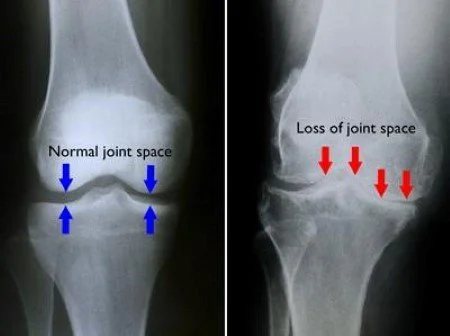

Comparison of knee X-rays showing normal joint space on the left and reduced joint space indicating joint loss on the right.

Knee Arthritis (Total Knee Replacement)

Arthritis in the knee can make everyday activities—like walking or climbing stairs—painful and difficult. A total knee replacement resurfaces the worn-out parts of the joint with metal and plastic components designed to move smoothly and reduce pain while improving strength and stability.